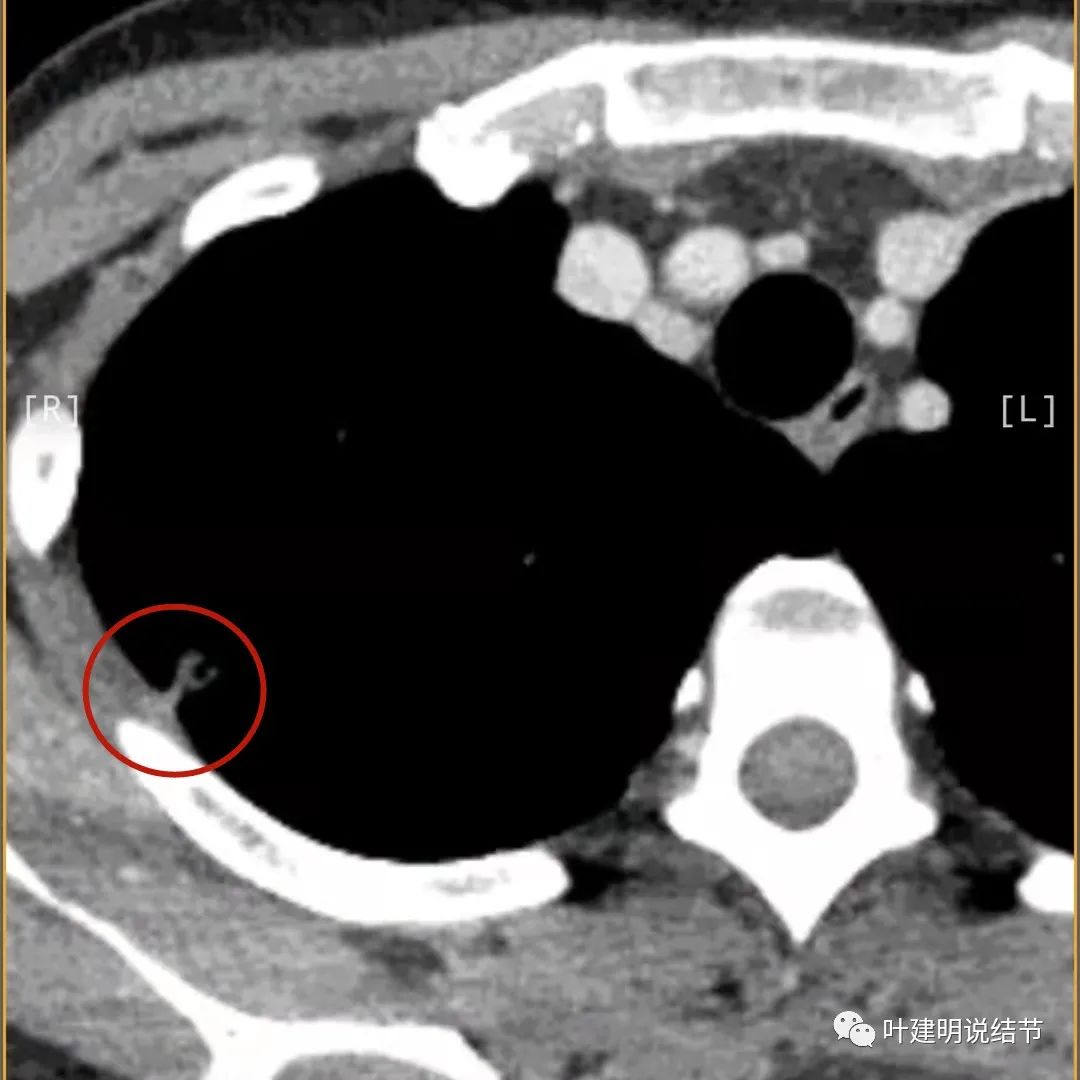

上面是她提供的病史资料,其中最重要的是PPD强阳性!其他主要看影像,我们先来看她2020年7月份的平扫片子(由于片子较多,详细展示是为了同道分析,我在影像特征描述上将只选取部分加以说明):

右肺尖偏实性结节(粉色箭头),邻近胸胸膜明显增厚不平,且广基附在胸壁上(蓝色箭头)